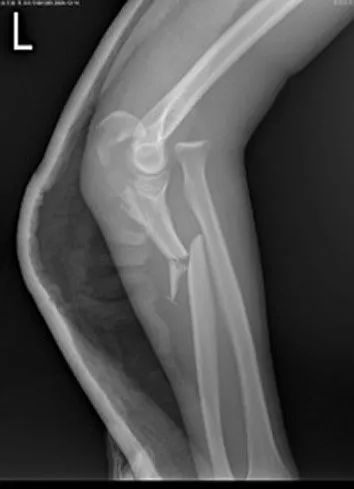

物理学改善我们生命的质量。仅就热力学现象的认识所带来的温度的概念和温度测量的实现,就不知道挽救了多少生命。光学成像原理的研究让许多人的视力问题得到精确的校正。X射线透视让骨骼损伤、肺结核之类的组织变异一目了然,而近些年才普及的X射线CT扫描、核磁共振等技术则让诊断具有无损、精确、多维等特点(图3),让发生在颅脑部、椎体部等活检取材不易或不可能的疾病得以快速诊断。此外,分子水平上的药物设计和制造得以实现的关键物理技术是大质量探测范围的质谱仪。在各种物理学设备更多地进入疾病诊断领域的时代,显然对医生进行充分的物理学培训(从设备原理的角度)是必要的。2007年发生在杭州的记者到几家医院踢馆的事件,反映的基本事实是,现代医生对其使用的诊断仪器显然缺乏起码的认识。

图3  X射线造影和CT扫描技术让伤病诊断可视化、定量化